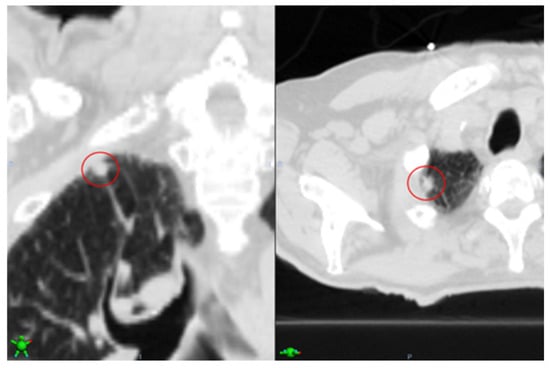

We are aware that our study may have a few limitations. First, as seen in Table 3, we see two cases (6 and 10) with false negatives (FN), which is highly undesirable. Upon further analysis, we realized that for case 6, the reason that the segmentation model did not detect the nodule is that, (i) as seen in Figure 5, the nodule is very close to the lung wall, making the nodule detection very challenging, which has also been reported by previous works [13]; (ii) currently, our model is designed as a standalone nodule detector, thus it is restrictive to detect fewer FPs, which resulted in some True Positives being filtered out. With the EHR-extracted information and lowering the classifier threshold, the issue is resolved.

Figure 5. Case 6 where the nodule is very close to the chest wall, making the nodule detection very challenging. Left showing the coronal view, and right axial view, with tumor marked with red circle.